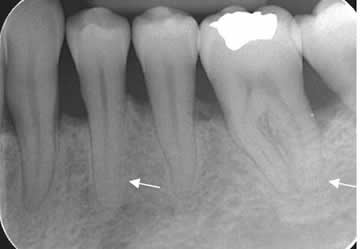

Fig 40. Enfermedad periodontal.

Rx periapical. Pérdida en la nitidez de los contornos del ligamento periodontal, por inflamación incipiente.

Fig 41. Enfermedad periododontal.

A y B: Rx periapical. Incremento del espacio periodontal, con lucencia que rodea las

raíces dentales y corresponde a bolsa periodontal.